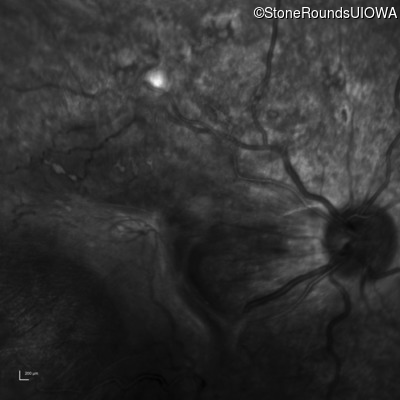

Infrared Fundus Photograph - Right - Count Fingers 3'

Exemplar